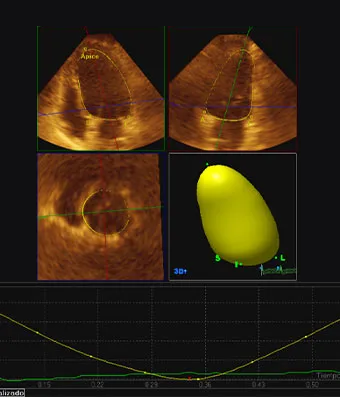

El ecocardiograma o ecocardiografía utiliza ondas sonoras de alta frecuencia para obtener imágenes del corazón en vivo y que son proyectadas en una pantalla. Este auxiliar diagnóstico aporta información en 30 a 60 minutos de la forma, tamaño, función y movimiento del corazón así como de sus estructuras internas, como por ejemplo las válvulas cardiacas. Este estudio es seguro en pacientes adultos, en pacientes pediátricos (ecocardiograma pediátrico) o incluso en mujeres embazadas para estudiar el desarrollo del corazón del bebé en la cavidad uterina (ecocardiografía fetal).

Las imágenes ecocardiografías del corazón pueden ser obtenidas en diferentes modos (unidimensional, bidimensional o tridimensional, Doppler, Doppler color), utilizando una sonda externa (ecocardiograma transtorácico) o una sonda interna (ecocardiograma transesofágico) y puede ser adquirido en reposo, en estrés con esfuerzo físico o con el uso de medicamentos (estrés con dobutamina), dependiendo del diagnóstico y de la indicación de tú médico.